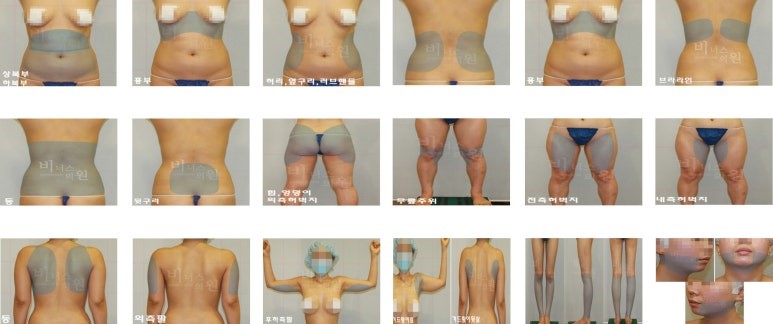

아래 사진은 수술 당일과 수술 후 1주일 경과 시기의 모습으로, 멍과 부기가 남아 있을 수 있는 회복 초기 단계의 과정입니다. 회복 속도와 멍 정도는 개인차가 있을 수 있지만, 대부분은 일상생활에는 무리가 없으며, 팔뚝의 변화는 1개월, 3개월, 6개월에 걸쳐 점진적으로 개선이 됩니다.

| 게시된 지방흡입 전후사진 정보 | |||

|---|---|---|---|

| - 동일인여부 | 비너스의원에서 수술하였으며 동일인임 | - 촬영시기 | 2025년 촬영 수술후 1주일 경과비교 |

| - 동일 조건 | 최대한 동일한 자세와 크기로 편집함 | - 부작용 정보 | https://myvenus.co.kr/251242 |